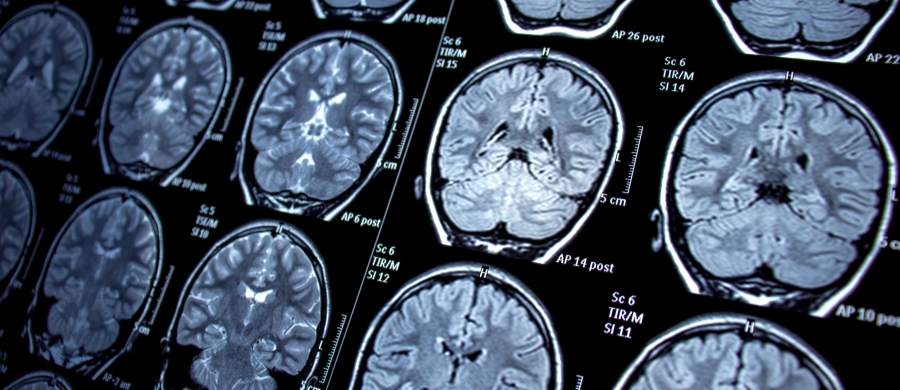

A epilepsia é uma condição neurológica que afeta milhões de pessoas em todo o mundo....

O uso da Cannabis Medicinal para Epilepsia